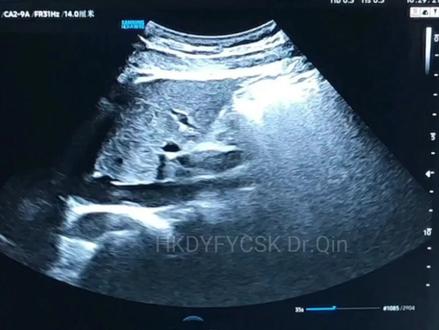

下腔静脉的测量啊,咱们与下腔静脉汇入口远心端约两厘米那个位置进行测量。下腔静脉的内筋,下腔静脉的塌陷,塌陷率。咱们又 呼气末的下强筋脉内筋,然后减去吸气,嗯,吸气的下强筋脉内筋,然后除以呼气的下强静脉内筋,也就说用他的最宽地方减去最窄的地方,然后除以最宽的地方。

最近两年,下腔静脉被大家广泛关注,尤其是在 icu, 这已经成为常规的测量项目。我们除了长轴上可以观察下腔静脉的内径以及塌陷率以外,我们还可以利用下腔静脉的短轴切面, 这更方便于我们判断下腔静脉的一个张力情况,有时见出下气面扫查受限。我们也可以换个角度,以肝脏作为声窗来观察下腔静脉的长轴以及他的短轴。